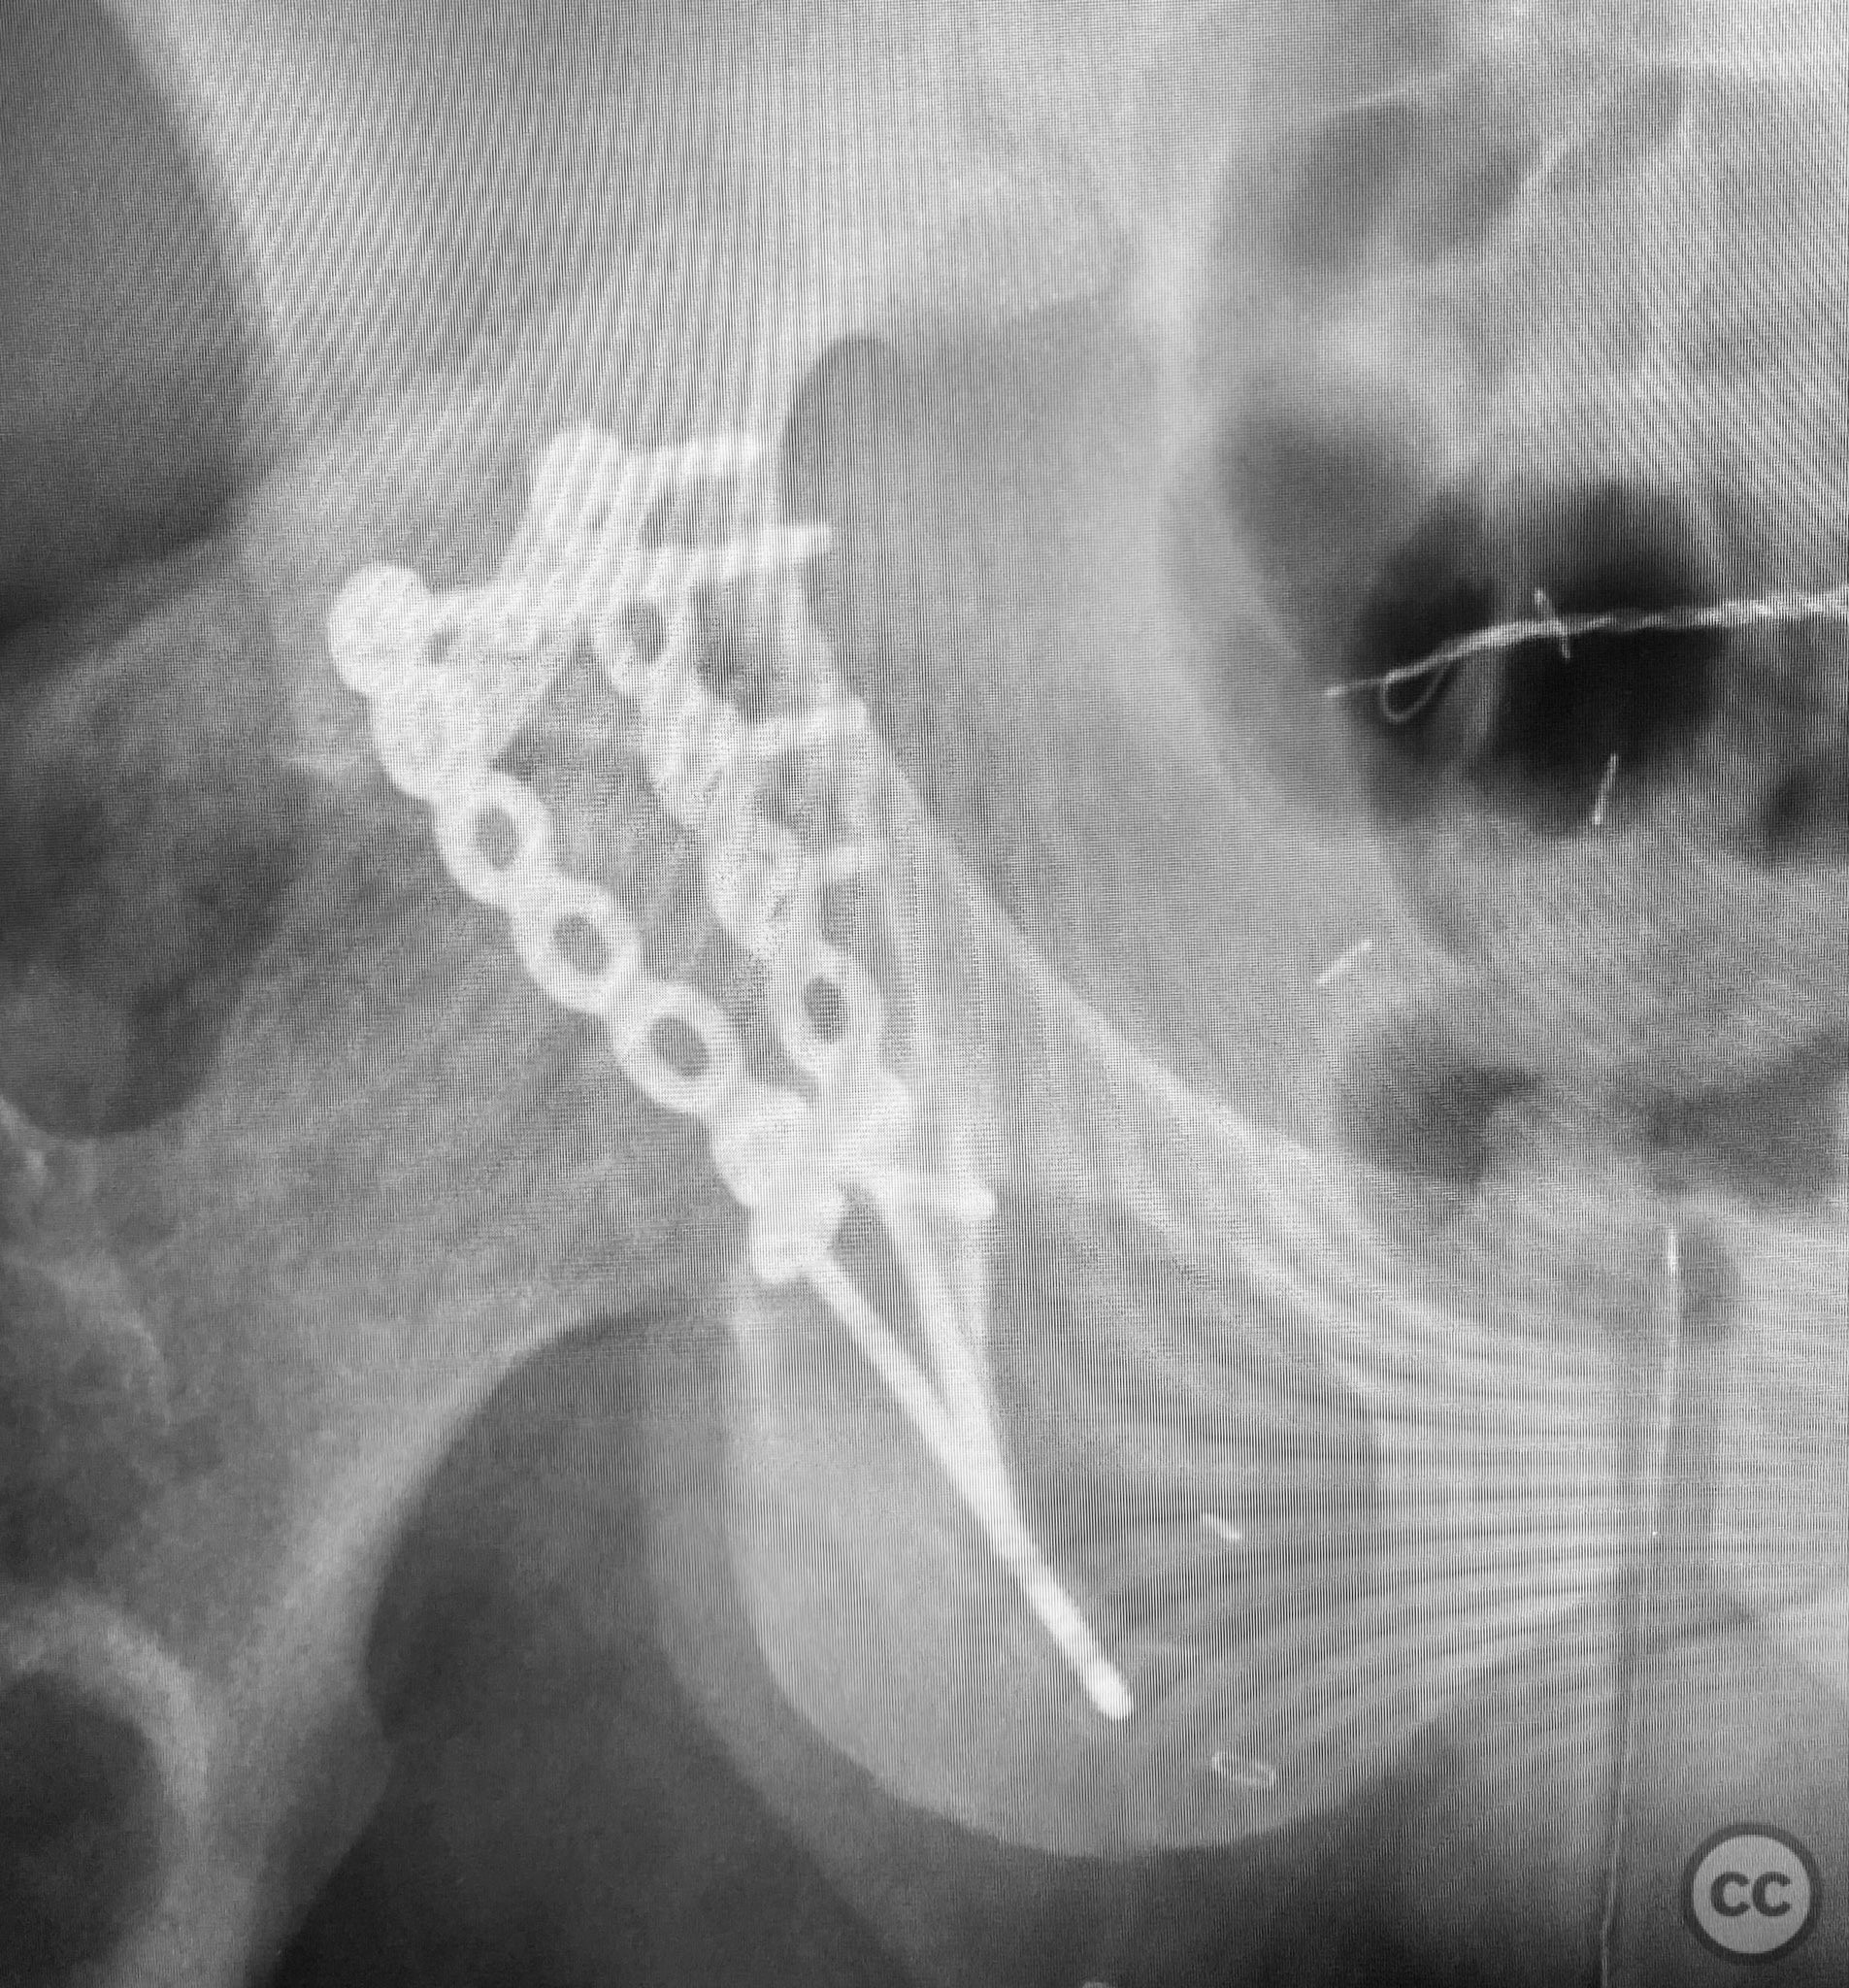

Anatomical surgical approach:  A standard Kocher-Langenbeck approach was performed: a longitudinal incision centered over the greater trochanter, extending proximally along the posterior iliac crest and distally along the femoral shaft. The fascia lata was incised, and the gluteus maximus split in line with its fibers. The short external rotators and piriformis were identified, tagged, and released to expose the posterior column and wall of the acetabulum. The sciatic nerve was identified in the greater sciatic notch region; intraoperatively, it was found to be severely contused, displaced, and uniquely penetrated by a sharp posterior wall fragment. Neuroplasty was performed, freeing the nerve from impalement and surrounding scar tissue. The intra-articular fossa acetabuli fragment was extracted, anatomically reduced, and stabilized along with other posterior wall fragments. A spring hook plate was applied to secure the cranial wall fragment due to its size and comminution.

Operative remarks:

Intraoperatively, the sciatic nerve was found to be not only contused but also impaled by a displaced posterior wall fragment—a rare occurrence in acetabular trauma. Careful neuroplasty was required to release the nerve from direct bony penetration without further iatrogenic injury. Reduction of all articular fragments was achieved under direct visualization, with particular attention to restoring congruity of the acetabular rim and fossa. The use of a spring hook plate provided necessary buttress for the large cranial wall fragment, which could not be adequately stabilized with standard plating alone.

Orthopaedic implants used:   3.5mm reconstruction plate, spring hook plate